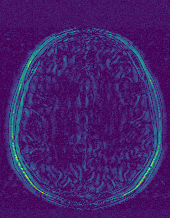

6.2.2 Quality of the Predicted Edges

EPN is utilized to provide edge priors for later reconstruction, so the quality of the predicted edges is very important. In Fig. 10, we provide some qualitative results of the predicted edges of EPN on three multi-coil datasets. Among them, the GT edges are extracted using the Sobel operator. As can be seen from the images, our proposed EPN can predict an approximate contour for the overall subject and can reconstruct accurate edges close to the GT edges under two acceleration factors. This fully verifies the effectiveness and excellence of the proposed EPN.

(a)

(b)

(c)

(d)